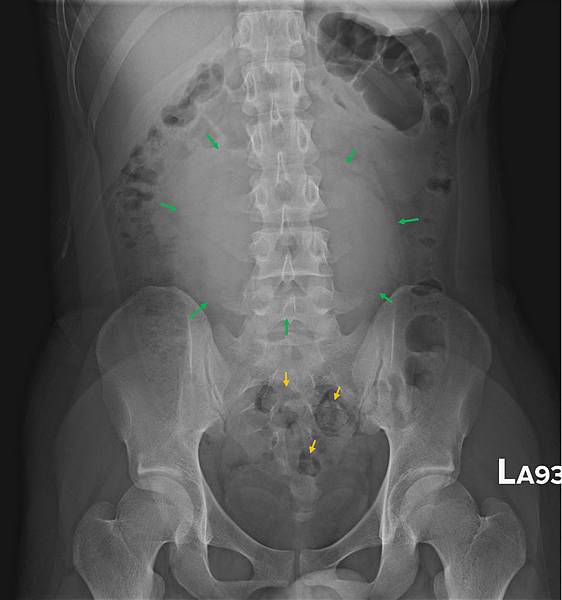

CXR才是診斷的經典:

右側橫膈下方有經典的Free air,

是胃/十二指腸或小腸或大腸破了!一個胃或腸的小破洞,電腦斷層無法判定哪兒破了,一般外科開下去發現是遠端降結腸(Distal descending colon)破了一個洞(0.5 cm),於是找直腸外科繼續完成手術。

她的早期診斷是結腸憩室炎,拖了十幾天破掉,如果一週前就去看病,診斷出來用抗生素治療,她就不必開刀先做人工肛門,然後再開一次刀把大腸接回去,住院折騰兩個多月。新冠疫情下,即使是有錢人生病也會忍著看會不會自己好起來。wleemc 發表在 痞客邦 留言(9) 人氣(612)